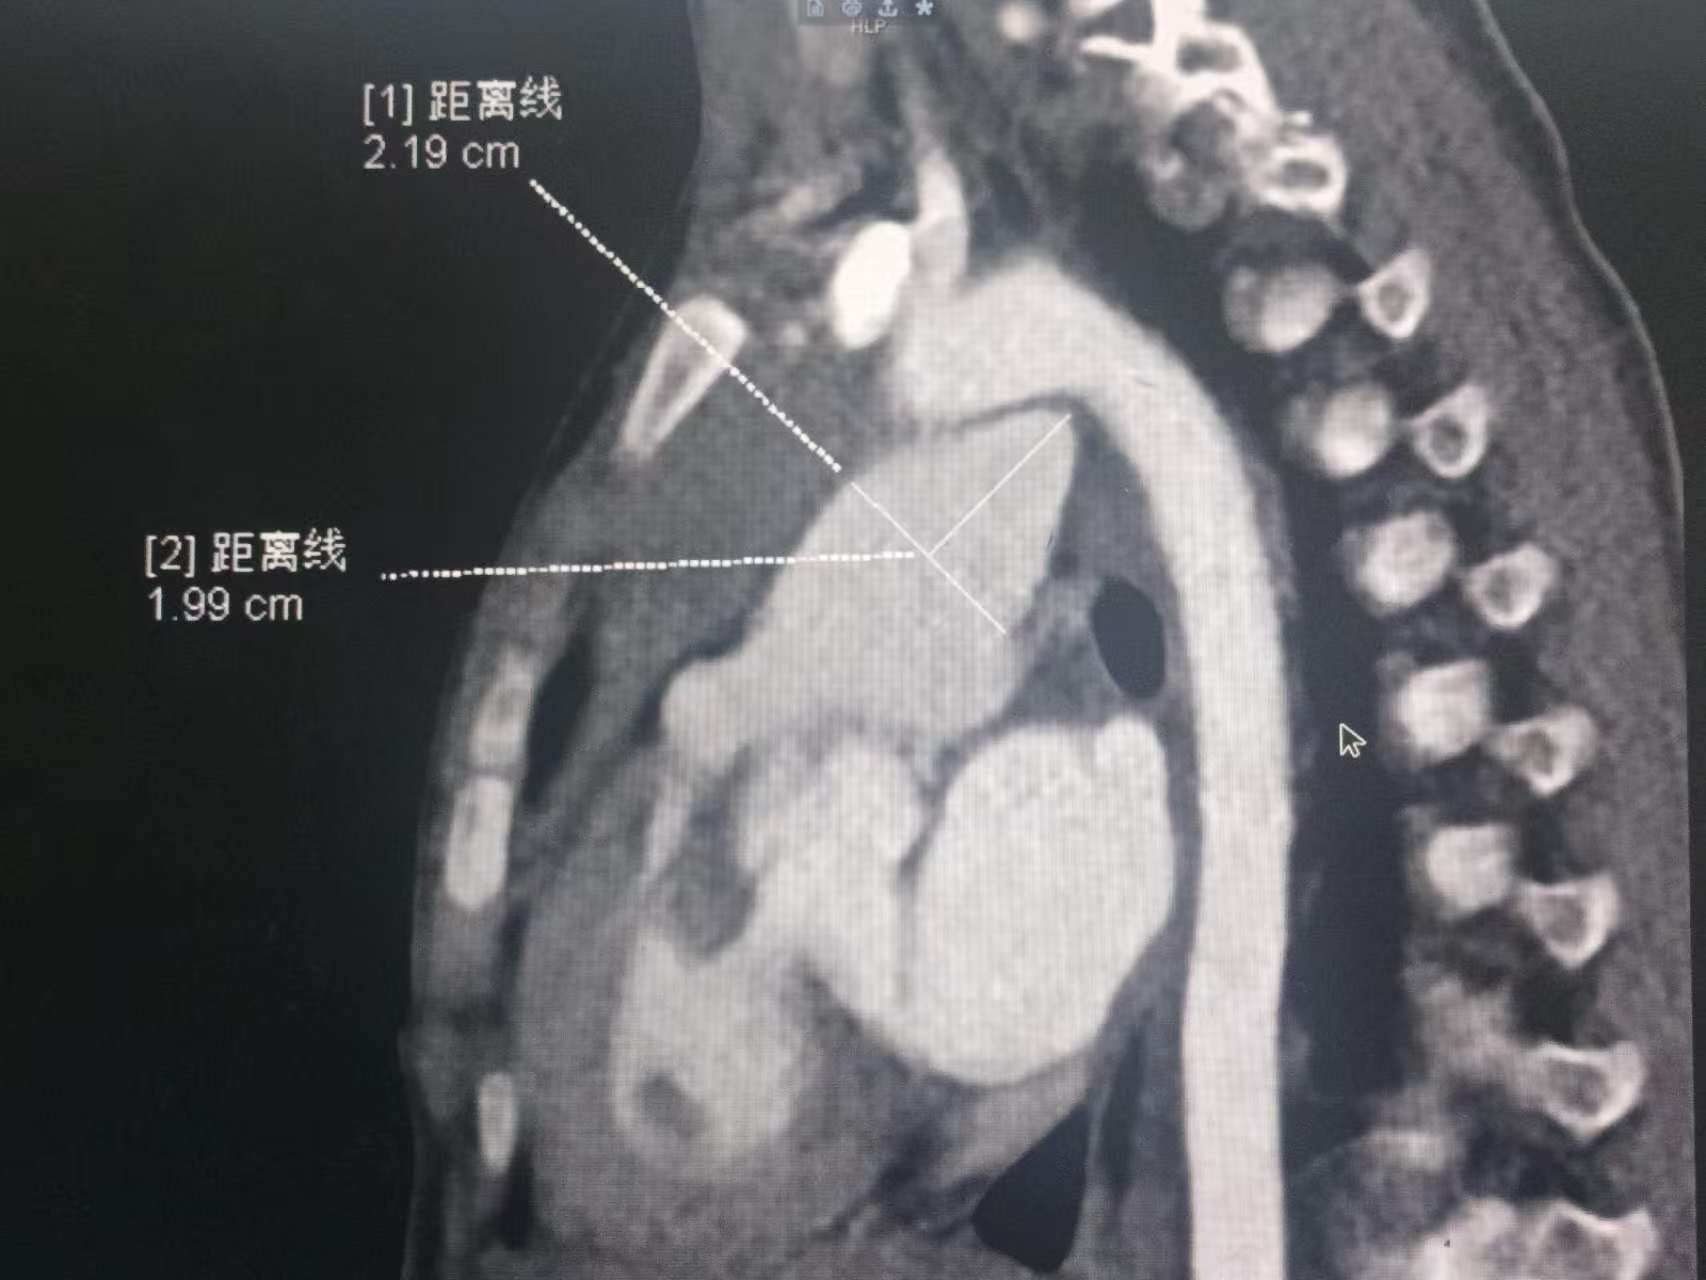

据悉,动脉导管憩室在临床上较为罕见。从胚胎发育机制看,动脉导管通常在出生后逐渐闭锁。而在少数情况下,该部位在闭合过程中局部膨出,形成憩室结构。该结构不仅本身脆弱,还会加剧心脏血流动力学紊乱。本例患儿的特殊性在于集三种心脏畸形于一体,这些畸形共同导致患儿心脏血流异常,影响其生长发育。

动脉导管憩室